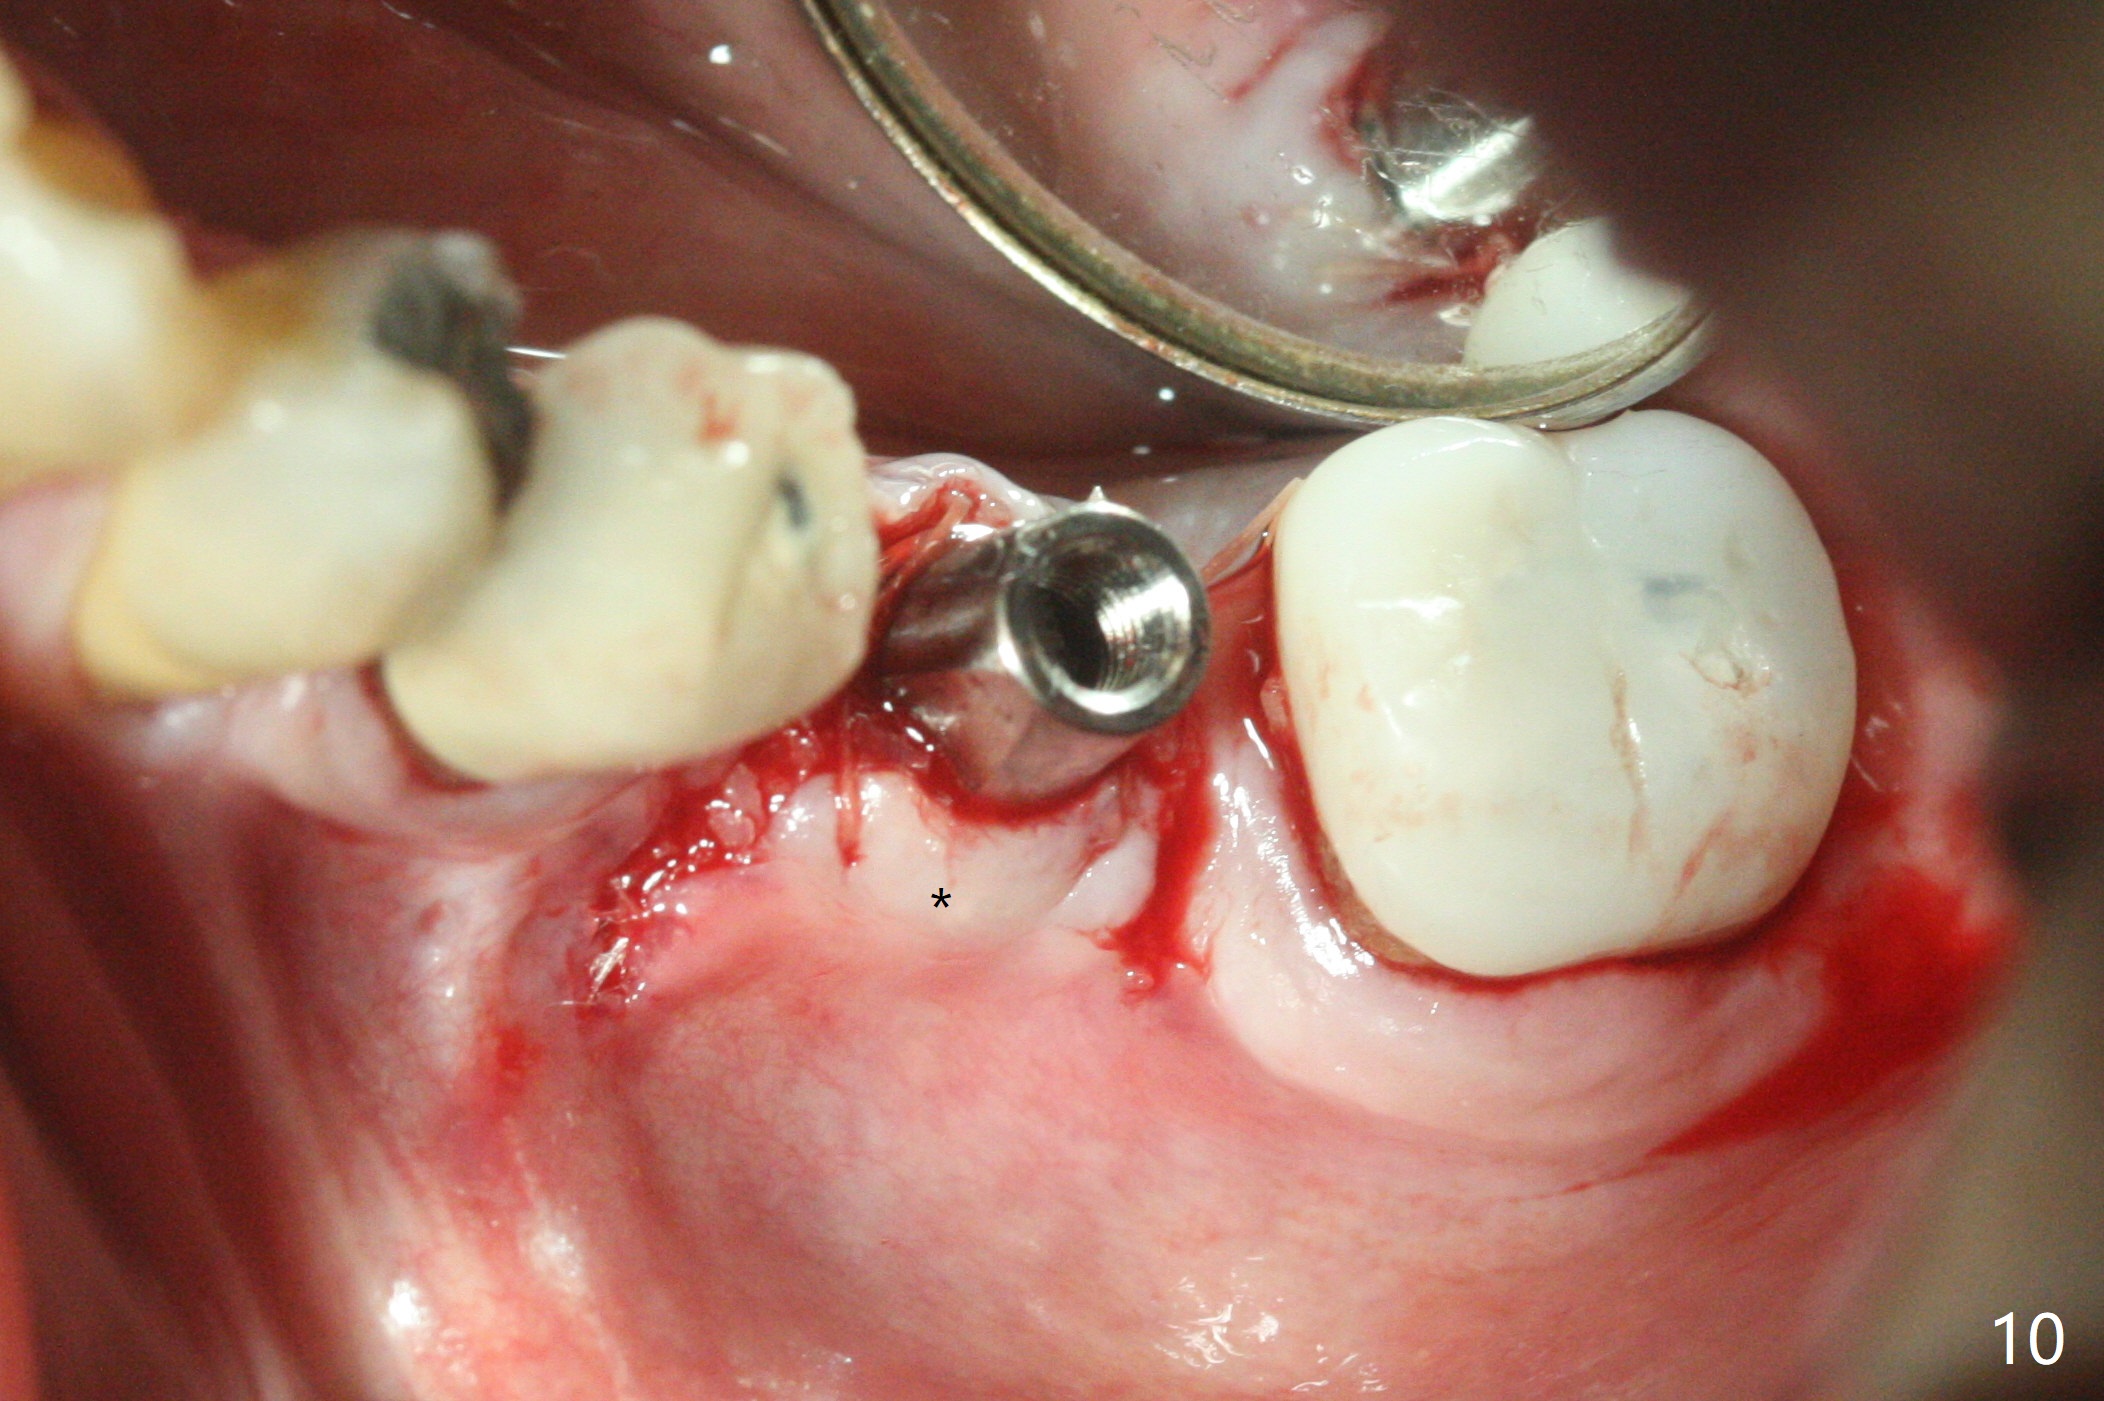

When the patient returns 4 months post implant removal and bone graft, the ridge at #19 is concave with a small hole which communicates with the underlying bone (Fig.1 <). The low density bone in the middle of the socket is ignored (Fig.2 *, 3 S (soft)). With under drilling, primary stability of tissue-level taps is lower. A bone-level dummy implant is placed with low torque (Fig.4). After removal of granulation tissue distal to the osteotomy, a larger implant is inserted with ~15 Ncm; mixture of autogenous bone and allograft is packed (Fig.5 *). The latter is covered by 12x12 mm BioXclude and sutured with 4/0 Chromic Gut tension free. 植牙后6.5月牙槽嵴饱满,角化龈宽(图六(刚开始浸润麻醉))。术后6.5月切开证实植体上面没有骨质覆盖(如图七:*),第一螺纹可能暴露(>)。由于骨质吸收,大号基台置入没阻挡,或者困难(图八),第一螺纹暴露(>)需要再次植骨(图九:*)。放置大号基台(6x6(4)毫米)和植骨使萎缩牙槽嵴部分得到修复(图十,与Uncover前(图六)对比)。Uncover时即刻置入修复性基台好处是利用基台牙龈外部分强化牙周敷料固定,基台中央放置一个棉球后,敷料可以插入基台中央进一步增加固位(图十一(舌侧观):*)。